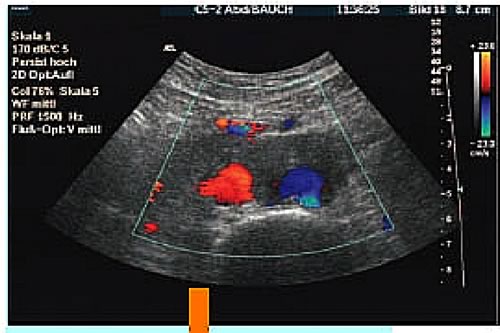

Figura 3: ecocolor doppler; massa fibrotica che circoscrive l'aorta e la vena cava inferiore.(Ultraschall Med 2005; 26: 91-93)